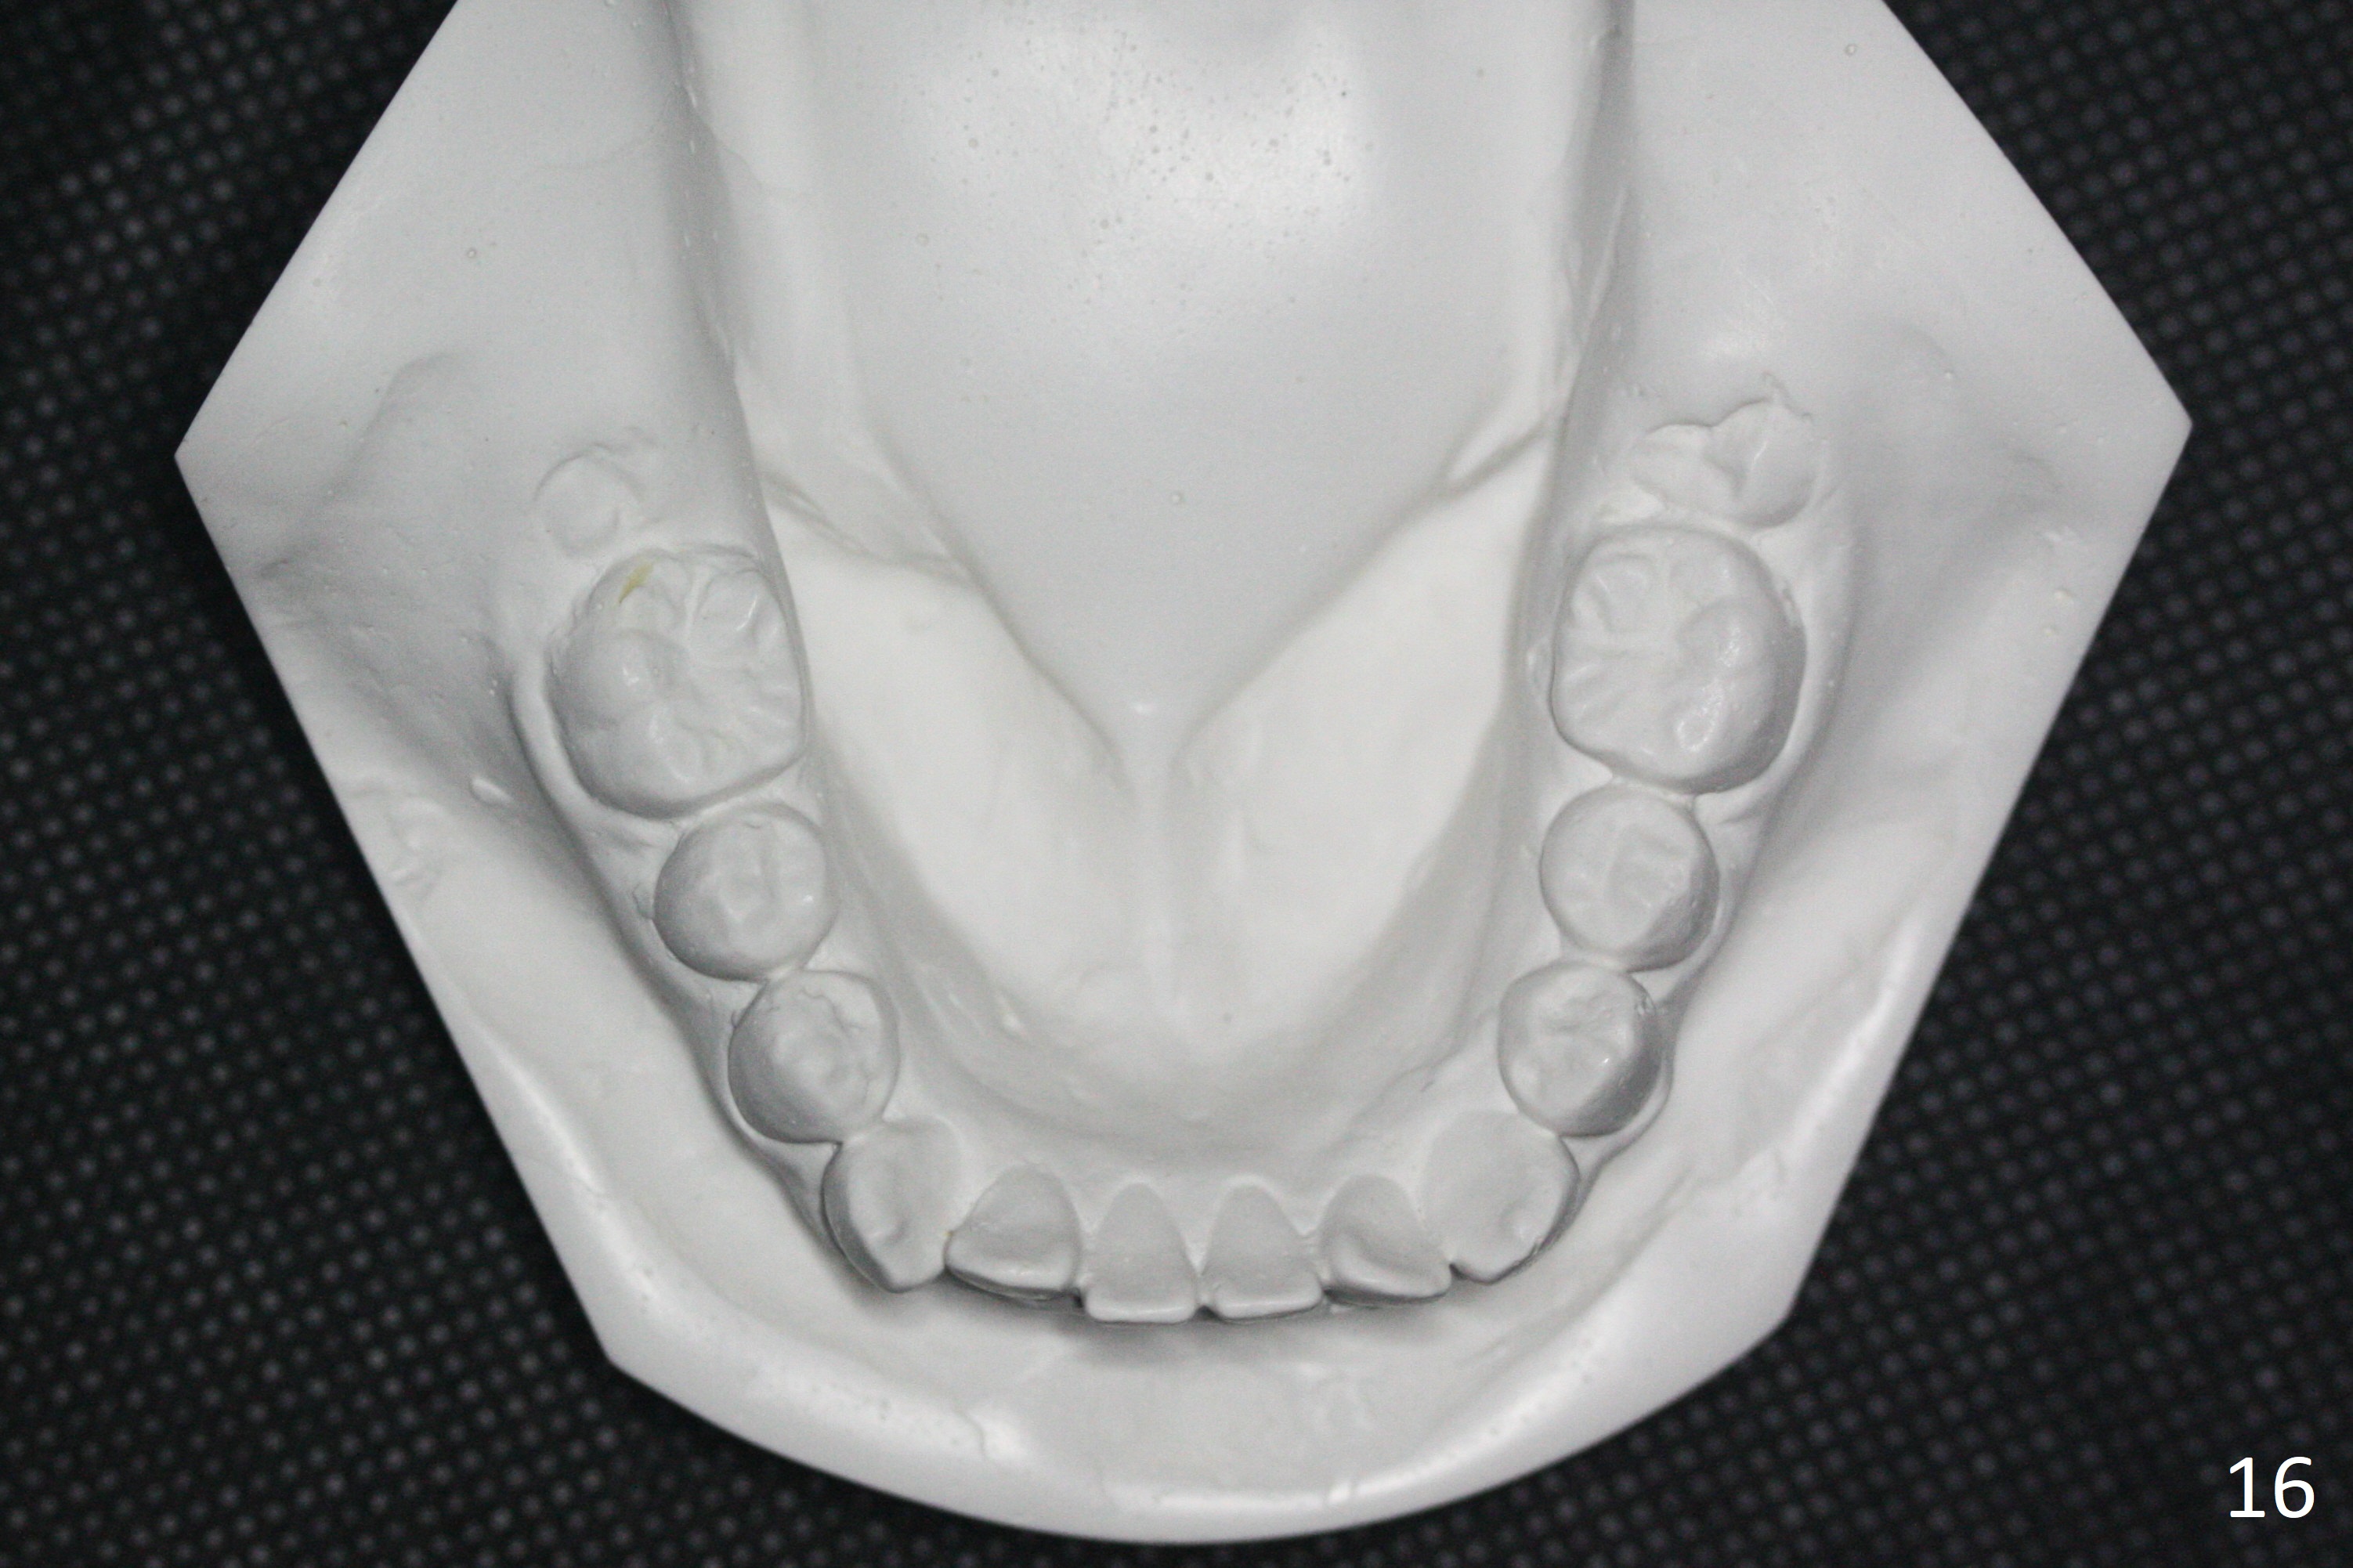

Shallow Overbite

A 12-year-old man has mild lip protrusion (Fig.1,6,7). Orthodontics will be conducted without extraction. Unlike his elder brother, the overbite is shallow. With anterior bracket differential (4-4-5 mm) and mild bimaxillary protrusion, open bite will be created? Or 4-4-4.5mm scheme should be adopted to avoid open bite?